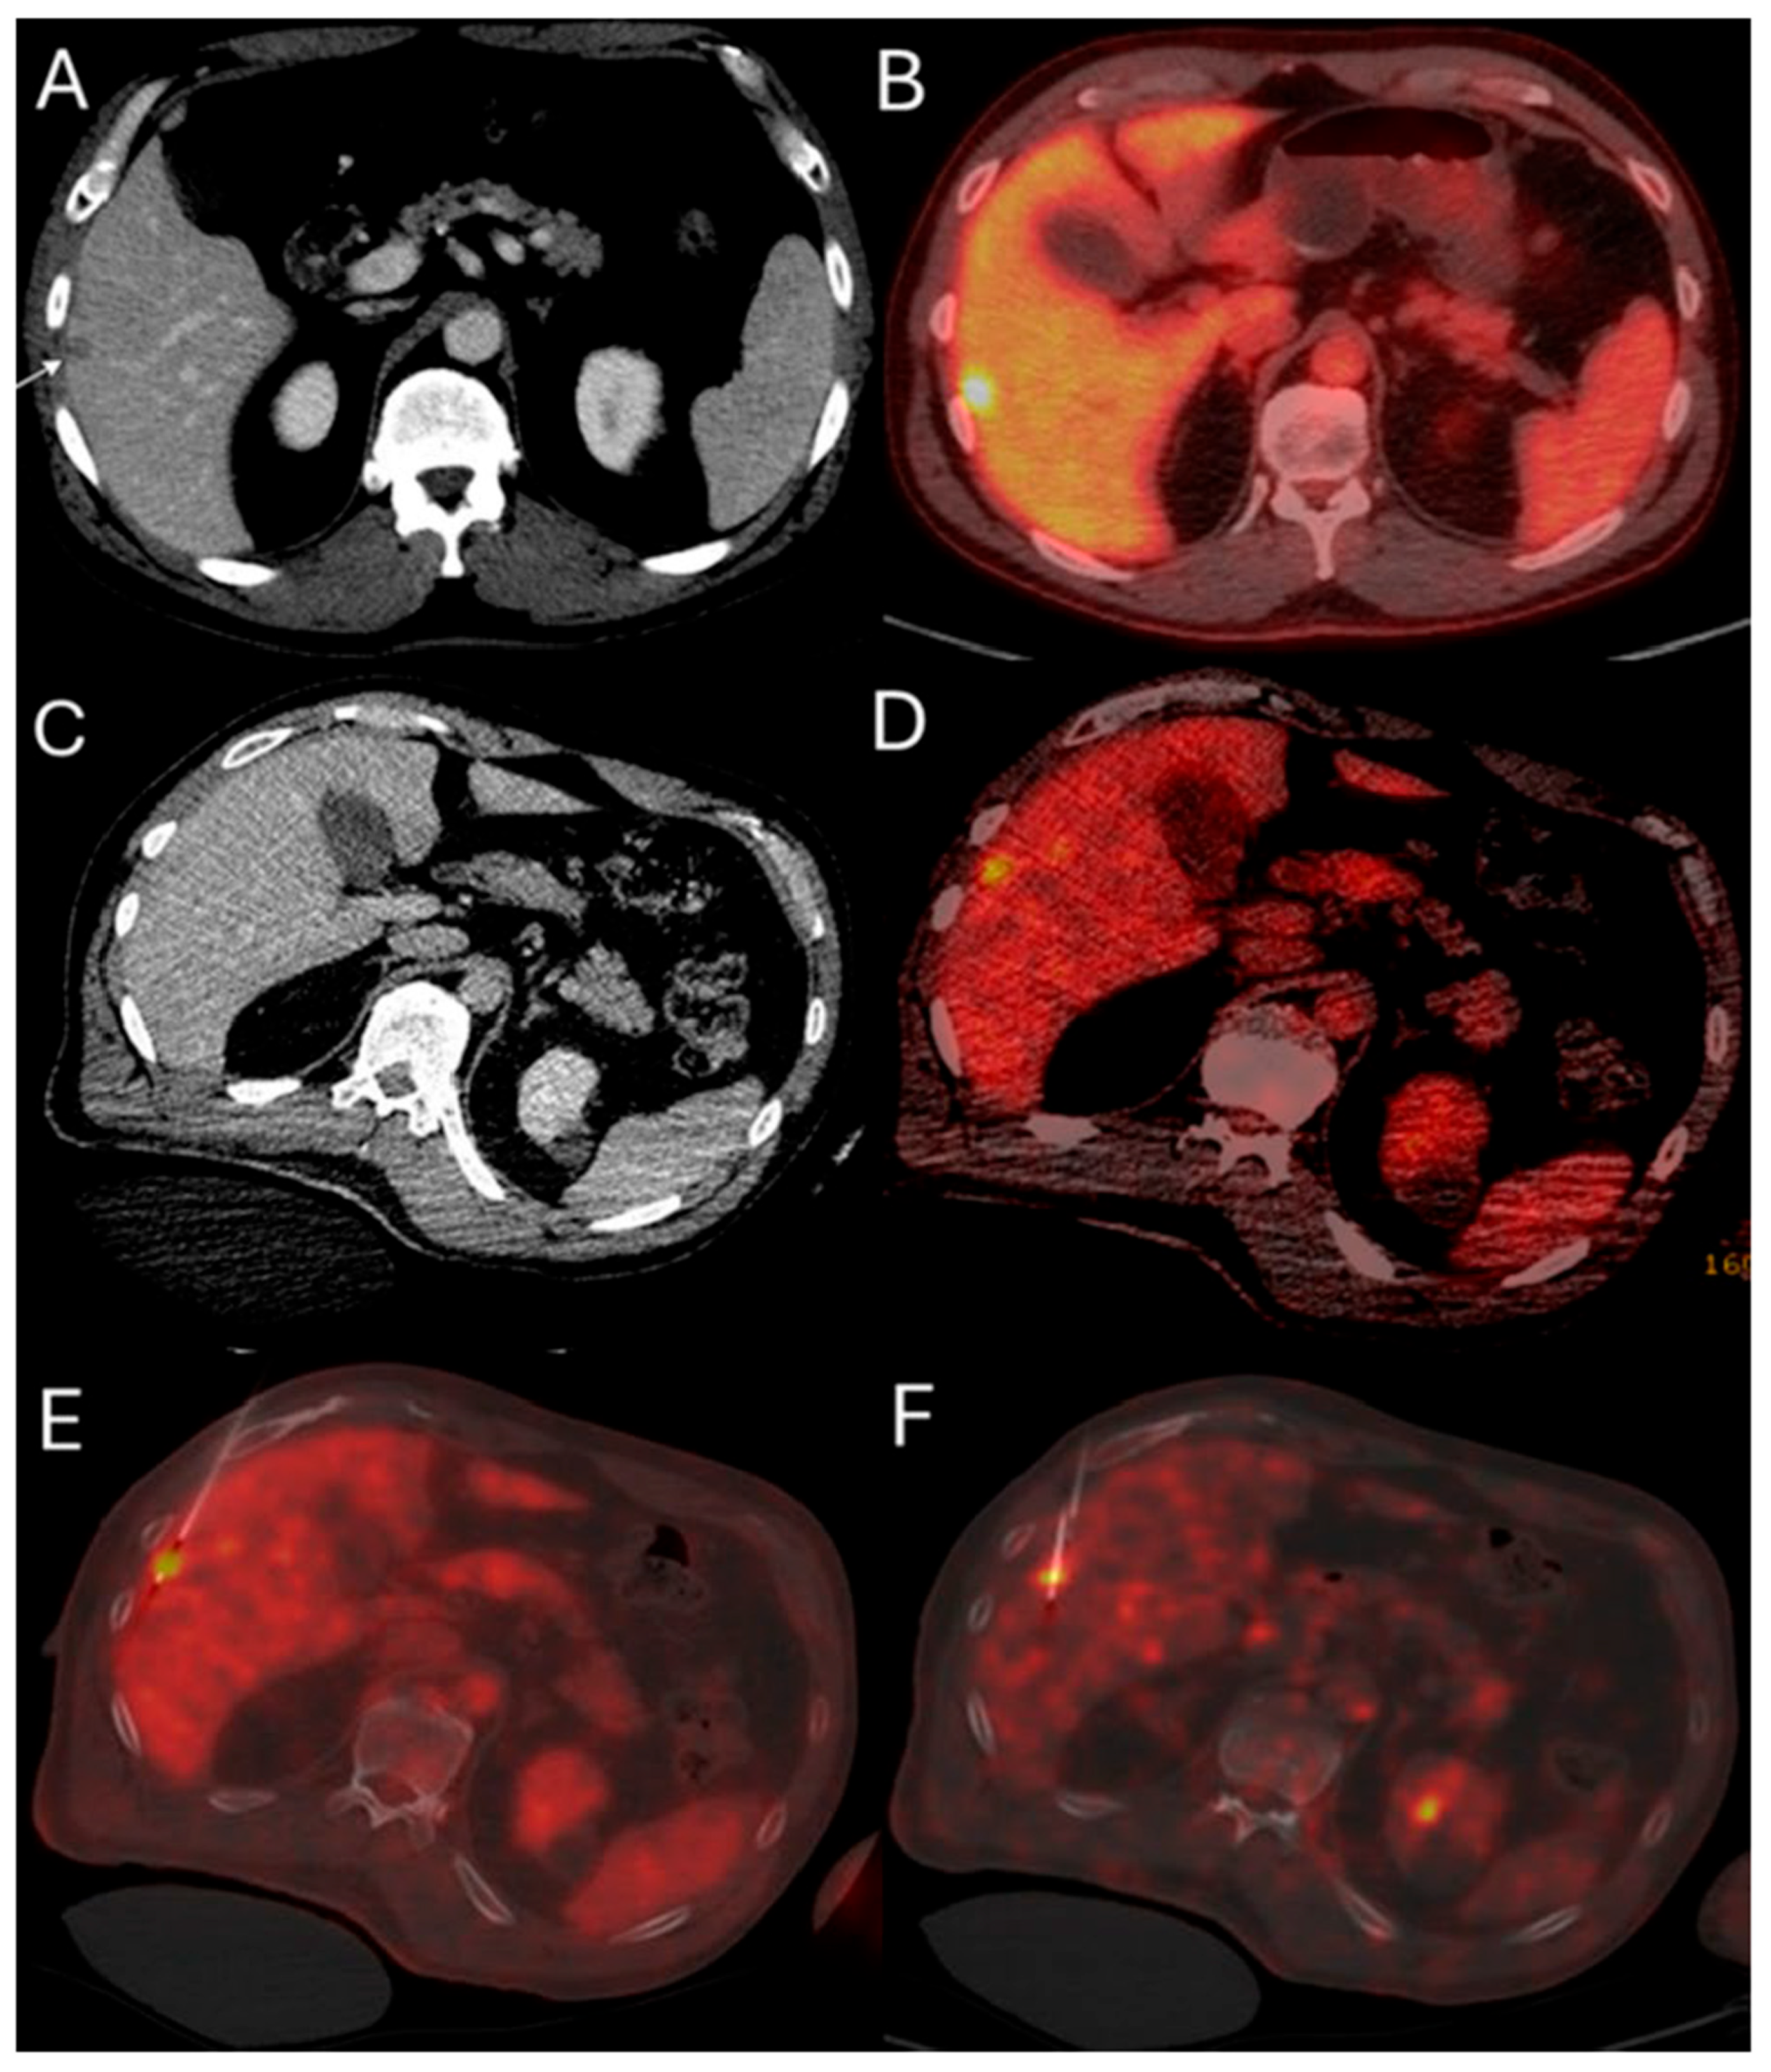

Figure 2.

51-year-old male with history of colorectal cancer undergoes MWA for new subcapsular liver metastasis in hepatic segment 5. Pre-ablation ceCT ((A) arrowhead) and FDG-PET/CT (B) demonstrate the tumor. The intraprocedural ceCT barely identifies the target tumor (C). Utilization of split-dose FDG PET/CT allows visualization, targeting, and monitoring of the FDG-avid tumor (D) with short acquisition 1 min breath-hold real-time scans allowing for accurate targeting for biopsy (E) and microwave ablation (F).